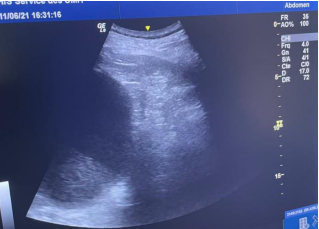

Ultrasound performed by the on-call urologist prior to nephrostomy drainage, revealing an anechoic cavity developed within the renal parenchyma.

Figure 3: Ultrasound performed by the on-call urologist prior to nephrostomy drainage, revealing an anechoic cavity developed within the renal parenchyma.